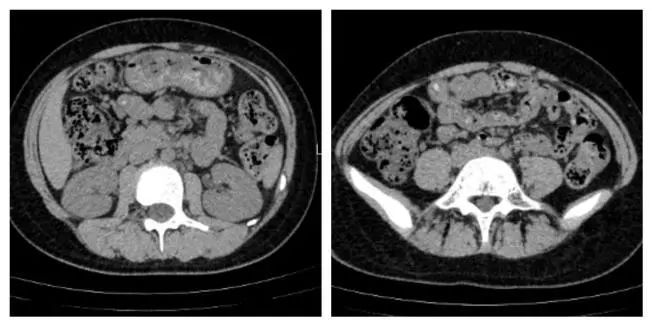

战场侦查

腹部 CT 提示急性阑尾炎并粪石形成。血常规提示白细胞显著增高,感染指标明显增高。